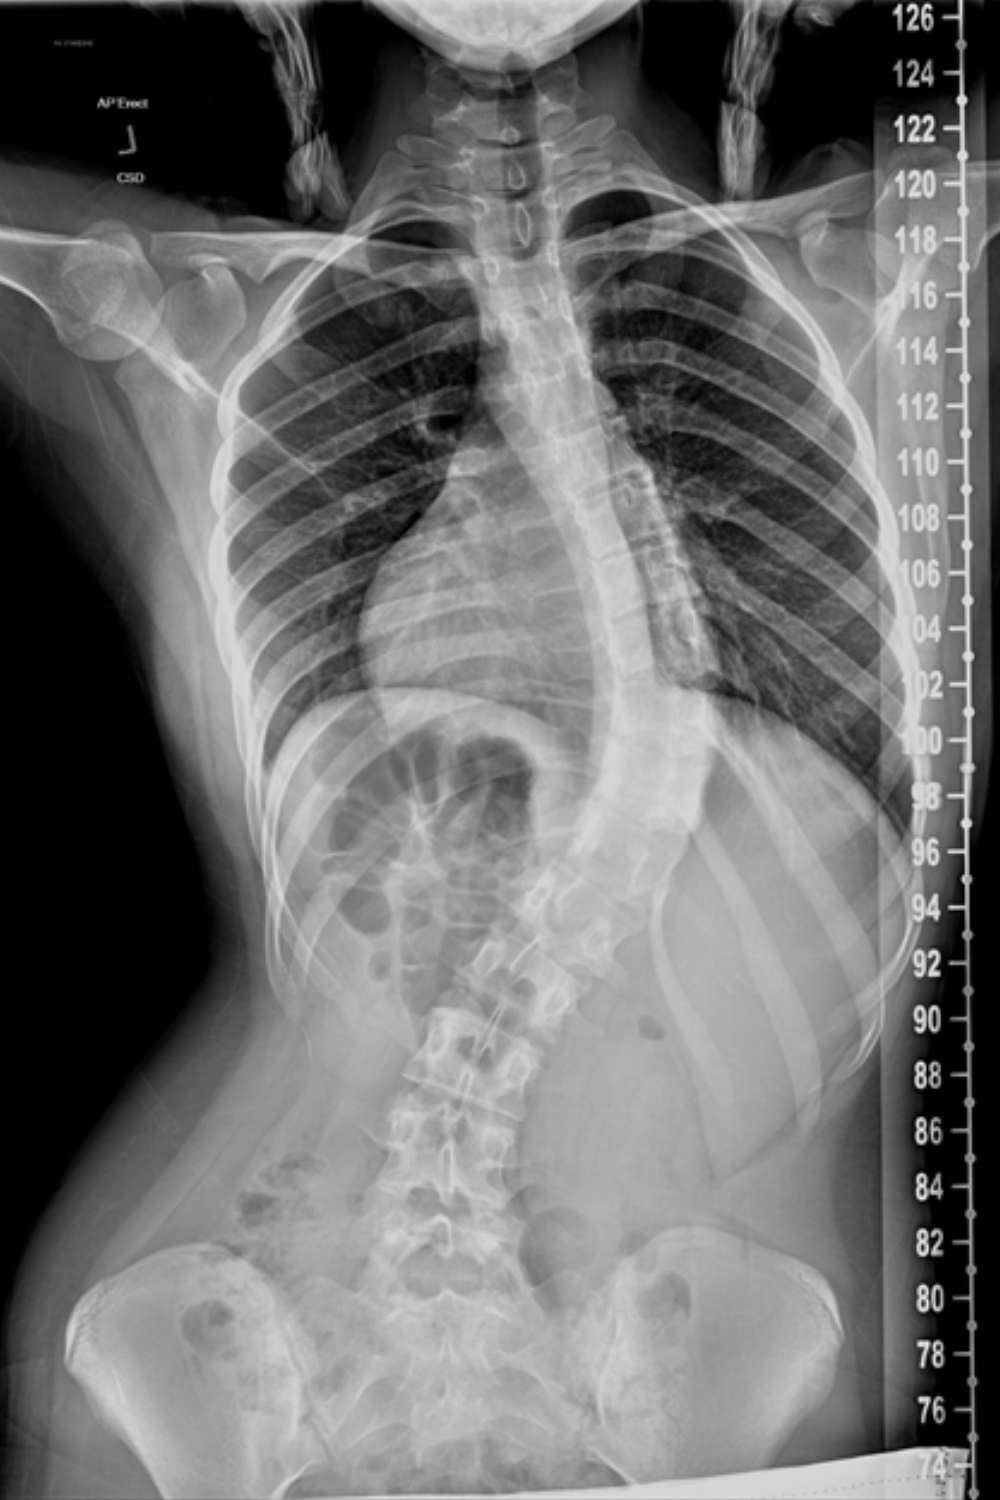

Below is a comparison of before and after images and x-rays of a teenager who underwent surgery due to her scoliosis:

Before |

|

![]() |